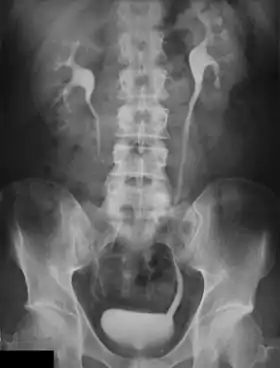

![]() An Example of an IVU radiograph | |

An intravenous pyelogram (IVP), also called an intravenous urogram (IVU), is a radiological procedure used to visualize abnormalities of the urinary system, including the kidneys, ureters, and bladder. Unlike a kidneys, ureters, and bladder x-ray (KUB), which is a plain (that is, noncontrast) radiograph, an IVP uses contrast to highlight the urinary tract.

An injection of X-ray contrast medium is given to a patient via a needle or cannula into the vein,[7] typically in the antecubital fossa of arm. The contrast is excreted or removed from the bloodstream via the kidneys, and the contrast media becomes visible on X-rays almost immediately after injection. X-rays are taken at specific time intervals to capture the contrast as it travels through the different parts of the urinary system.[7] At the end of the test, a person is asked to pass urine and a final X-ray is taken.[7]

Immediately after the contrast is administered, it appears on an X-ray as a 'renal blush'. This is the contrast being filtered through the cortex. At an interval of 3 minutes, the renal blush is still evident (to a lesser extent) but the calyces and renal pelvis are now visible. At 9 to 13 minutes the contrast begins to empty into the ureters and travel to the bladder which has now begun to fill. To visualize the bladder correctly, a post micturition X-ray is taken, so that the bulk of the contrast (which can mask a pathology) is emptied.